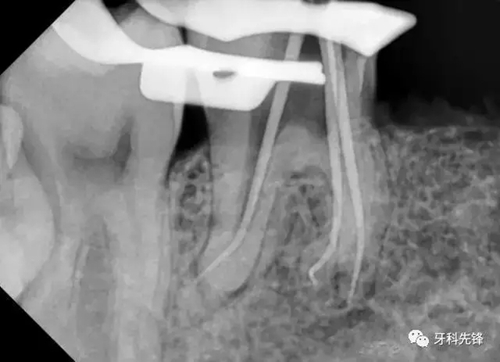

處置: 46右下牙槽神經(jīng)阻滯麻醉,46橡皮障隔濕,去凈腐質(zhì),開髓,拔髓,GG鉆擴(kuò)大根管口,根管疏通,根測,ML=19.5mm,MB=18mm,DB=DL=18mm,EDTA作用下M2鎳鈦機(jī)擴(kuò)至25#,試尖拍片,干燥根管,AHplus糊劑+牙塞尖+熱牙膠加壓根充,,聚羧酸鋅墊底,Z350納米樹脂充填,調(diào)合,拋光。